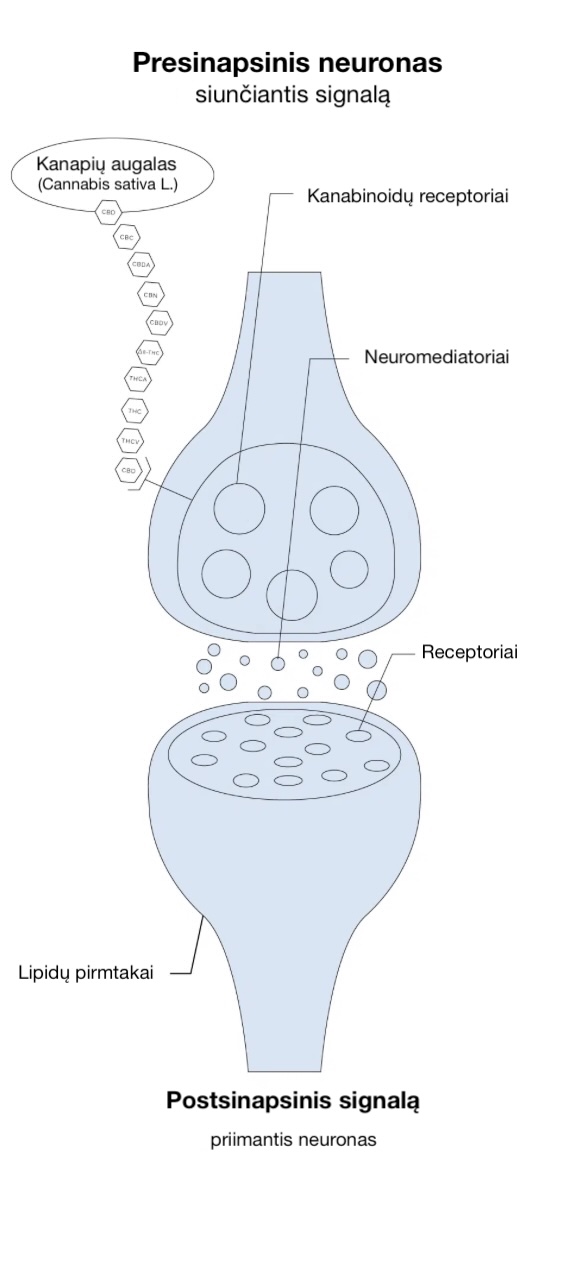

Kanabinoidų receptoriai

Kanabinoidų receptoriai yra žmogaus organizmo ląstelių paviršiuje ir „priima“ signalus iš išorinės ląstelės aplinkos. Jie perduoda informaciją apie pokyčius ląstelės viduje ir inicijuoja atitinkamas ląstelių reakcijas.

Yra žinomi du pagrindiniai kanabinoidų receptoriai — CB1 ir CB2. Jie nėra vieninteliai, tačiau buvo pirmieji atrasti ir iki šiol yra plačiausiai ištirti.

CB1 ir CB2 receptoriai yra pagrindiniai endokanabinoidų sistemos (ECS) elementai.

CB1 receptoriai daugiausia randami centrinėje nervų sistemoje, įskaitant smegenų neuronus, o CB2 receptoriaidažniausiai aptinkami už nervų sistemos ribų, pavyzdžiui, imuninės sistemos ląstelėse.

Endokanabinoidai

Endokanabinoidai, dar vadinami endogeniniais kanabinoidais, yra molekulės, kurias gamina pats žmogaus organizmas. Jos yra panašios į augalinės kilmės kanabinoidus, pavyzdžiui, CBD (kanabidiolį), tačiau natūraliai sintetinamos organizme.

Šiuo metu yra identifikuoti du pagrindiniai endokanabinoidai:

Anandamidas (AEA)

2-arachidonoilglicerolis (2-AG)

Šios molekulės padeda palaikyti organizmo vidinę pusiausvyrą (homeostazę), panašiai kaip ir CBD, ir yra gaminamos tik tada, kai jų reikia.

CBD veikia panašiai kaip šie natūralūs endokanabinoidai, padėdamas organizmui atkurti ir palaikyti natūralią pusiausvyrą, ypač situacijose, kai paties organizmo endokanabinoidų lygis yra sumažėjęs.

Metaboliniai fermentai

Metaboliniai fermentai apima FAAH ir MAGL, kurie yra atsakingi už endokanabinoidų skaidymą.

Fermentas FAAH skaido anandamidą (ANA), o MAGL — 2-arachidonoilglicerolį (2-AG).

Šie fermentai užtikrina, kad endokanabinoidai organizme būtų aktyvūs tik tiek laiko, kiek reikia, ir tiksliai reguliuoja jų veikimo trukmę.

Toks trumpalaikis veikimas skiria endokanabinoidus nuo daugelio kitų cheminių signalų organizme, pavyzdžiui, hormonų ar klasikinių neuromediatorių, kurie gali išlikti aktyvūs kelias sekundes ar net minutes, arba būti kaupiami ir panaudojami vėliau.

CBD produktai dažnai tiriami dėl jų sąveikos su šių fermentų veikla, nes CBD gali paveikti FAAH aktyvumą, padėdamas padidinti anandamido kiekį organizme ir taip sustiprinti jo teigiamą poveikį nuotaikai bei skausmo mažinimui.

Fitokanabinoidai, kurie gaminami kanapių (Cannabis sativa L.) augale, gali jungtis su endokanabinoidų receptoriais žmogaus organizme panašiai kaip ir paties organizmo gaminami endokanabinoidai.

Todėl natūralių, augalinės kilmės kanabinoidų įtraukimas į kasdienę profilaktiką ar gydymą gali pagerinti endokanabinoidų sistemos veiklą ir padėti organizmui atkurti natūralią pusiausvyrą.